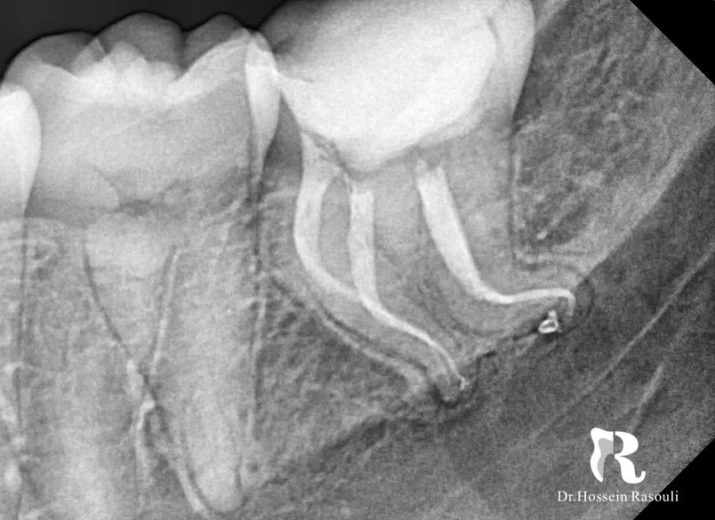

کانال‌های کِرو دار

Severe curve:mandibular second molar.